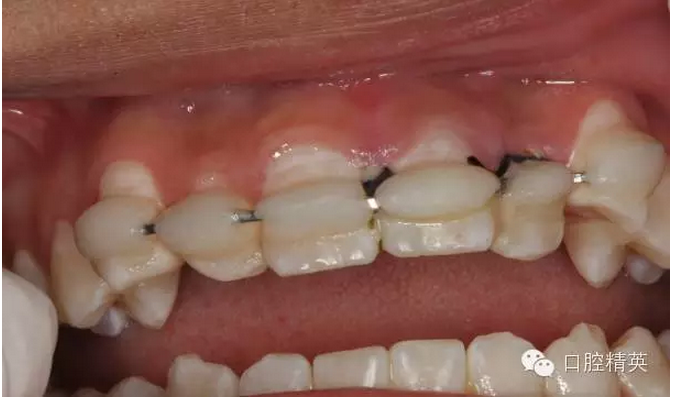

圖1.一周后復(fù)診拆線、唇側(cè)齦乳頭水腫。

圖2.拆線前腭側(cè)觀

圖3.拆線后唇側(cè)觀,牙齦乳頭輕度水腫

圖4.腭側(cè)觀21齦乳頭水腫明顯